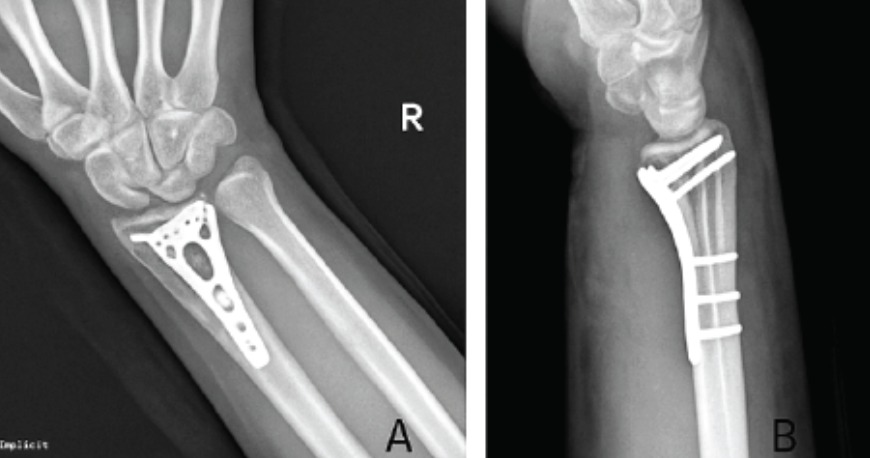

- Volar locking plate fixation (ORIF): The gold standard for surgical treatment of distal radius fractures. A pre-contoured plate is applied to the volar surface of the radius through a small anterior approach, capturing the distal fragments with locking screws that hold even in osteoporotic bone. Allows early mobilisation. Day case or overnight admission.